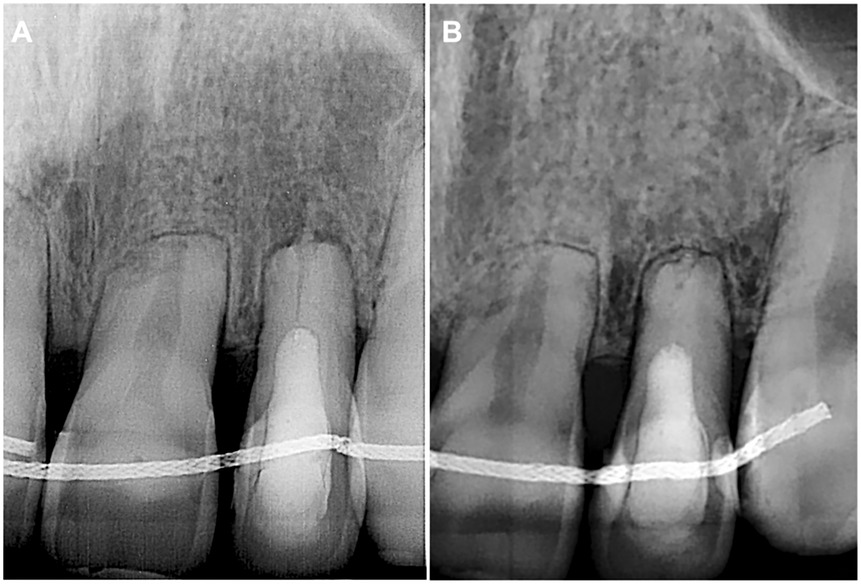

At the 3-month follow-up, the patient had no complaints, and no signs of endodontic pathology were observed. The follow-up radiograph showed periapical healing (Figure 4A). The next follow-up was scheduled for 6 months.

Figure 4. (A) Three-month follow-up periapical radiograph revealing a completely healed periapical lesion on tooth 22. (B) Four-year follow-up periapical radiograph demonstrating no signs of periapical pathology.

The patient returned after 4 years for endodontic treatment on a different tooth and reported no complaints for tooth 22. The absence of clinical signs for tooth 22 was equally followed by the complete healing of periapical tissues radiographically (Figure 4B).